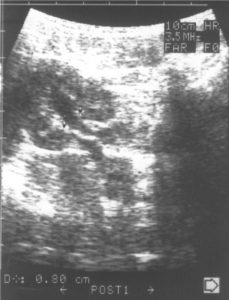

Фиг. 2. а/ – Пиелектазия – незначително отслояване на стените на бъбречното легенче, надлъжен срез и б/ Пиелектазия – напречен разрез на легенчето с предно-заден размер на дилатацията до 5 мм.

Специално прилагам УЗ образ /Фиг.2/ на това установено в УЗ образ на бъбреците при кърмачета отклонение, защото то е често срещано, но много рядко налага допълнителни изследвания.

Особено внимание ще отделя това най-често „малко” отклонение с наличие на незначително количество урина в пиелона – пиелектазия /Фиг.2/.